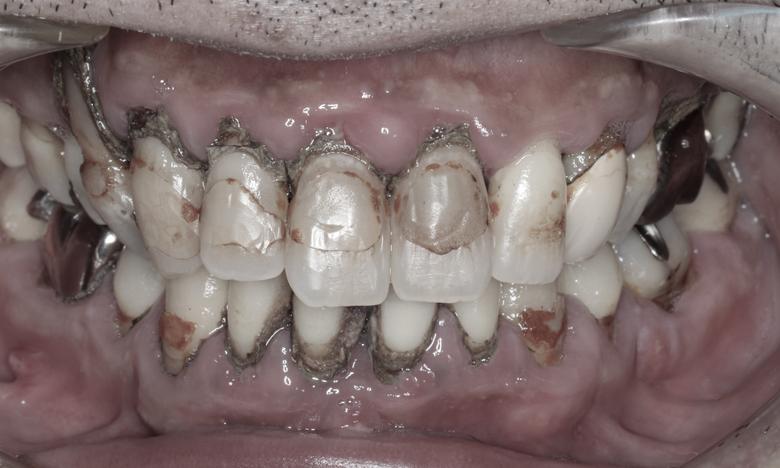

大病を患っていたことから口腔ケアが出来ず重度歯周病と歯冠崩壊が進んでしまったケースです。矯正治療とインプラント治療を組み合わせ、可能な限り天然歯を保存して口腔再建を行いました。